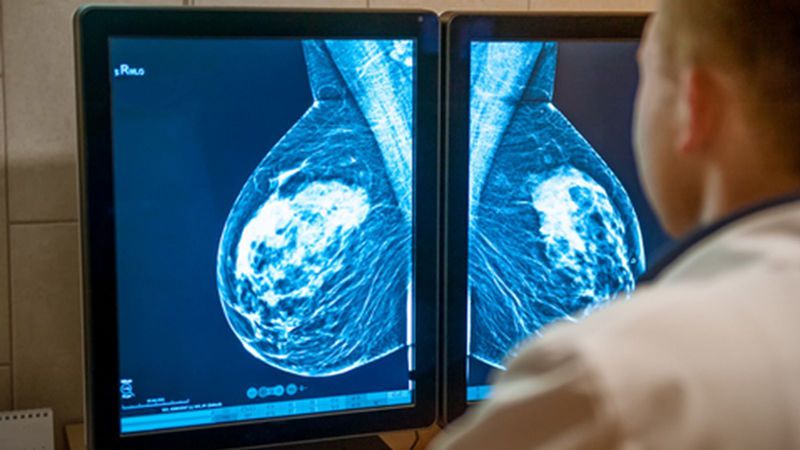

Doctors decide the stage of cancer as part of their prognosis. To confirm the degree of breast cancer, they check some of the various factors, together with tumor length. Doctors use several exams and examinations to assess the precise characteristics of a person’s breast most cancers. They use these records to assign values to the TNM staging device, in which: T is the dimensions of the primary, or number one, tumor N is whether or not cancer has spread to close by lymph nodes M is whether the cancer is metastatic, which means that that it has unfolded to distant components of the body The overall stages of cancer range from zero to 4. Stage 0 means that breast cancer is at a very early stage and has now not but spread. Stage 4 is past due-stage breast most cancer, which has unfolded to different parts of the frame. Every individual’s breast most cancer is exclusive. However, its stage gives a general indication of someone’s remedy options and outlook. People with early-level breast cancer are likely to have smaller tumors that are less complicated for medical doctors to treat. Larger tumors tend to suggest later-degree breast cancer, which can be more difficult to deal with.

Doctors measure the scale of the number one breast most cancers tumor at its widest point. They usually supply the size in millimeters (mm) or centimeters (cm). Subsequent gadget to grade tumor length: TX: The medical doctor cannot evaluate the primary tumor. T0: The medical doctor has no longer found evidence of a primary tumor. T1: The tumor is 2 cm (zero.79 inches (in)) or less in diameter. T2: The tumor is greater than 2 cm (zero. Seventy-nine in) but much less than 5 cm (1.97 in) across. T3: The tumor is bigger than five cm (1.97 in) wide. T4: The tumor may be of any size, but it’s far developing into the chest wall or skin. This class consists of most inflammatory breast cancers.